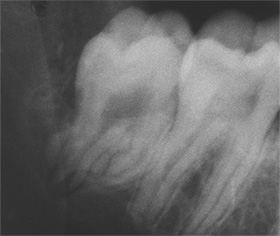

Der umfangreiche kariöse Defekt steuerte sehr bald hin auf die komplette Entfernung des Zahninnen­gewebes mit anschliessendem medikamentösen Wiederverschluss. Aufbissempfindlichkeit am Folgetermin ist immer Aufforderung zur erneuten Intensivsuche nach weiteren Kanälen, die hier einen 4. Ast zum Vorschein brachte. Nach 2 ausgelassenen Terminen

waren vorrangig Wiederherstellung von desinfizierender Einlage und provisorischer Füllung angezeigt. Eine weitere Woche später wurde in allen Kanälen das Medikament durch die endgültige Verschlussmasse ersetzt, worauf Zahn 36 mit 12-tägiger Verzögerung erneut zu rebellieren begann. Das hiess aus den hinteren Wurzeln Füllmaterial wieder raus und

Einlage erneut rein. Als es dann 4 Wochen später bei der hinteren Wur­zel aussen anzuschwellen begann und ein Medikamentenwechsel ohne Wir­kung blieb, wurden die hinteren Ka­näle abgefüllt und auch in gleicher Sitzung das überstopfte Material (Bild 1) mittels Resektion (Bild 2) von aussen entfernt.

Die ersten beiden Aufnahmen sind aus dem Jahr 1999, die 3. von 2006